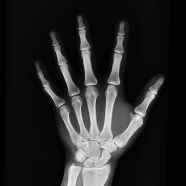

In the early 2000s, researchers in Dr. Gerard Karsenty’s group were studying a protein secreted by bones named osteocalcin (OCN) to see if it played a role in bone mineralization (i.e. how our skeleton attracts the minerals needed for its structure). Even though they found that OCN isn’t involved in bone mineralization, they noticed that mice lacking the gene encoding OCN were unusually docile [1]. This surprised the researchers because it implied that a component originating from bones had some effect on behavior and, thus likely the brain. Usually the only compounds secreted by peripheral organs (and yes, your bones can be considered an organ) to affect the brain are hormones, meaning that the researchers discovered that bones are hormone-producing organs. It’s wild to think that this realization happened so recently given how long we’ve had the opportunity to look and study skeletons.